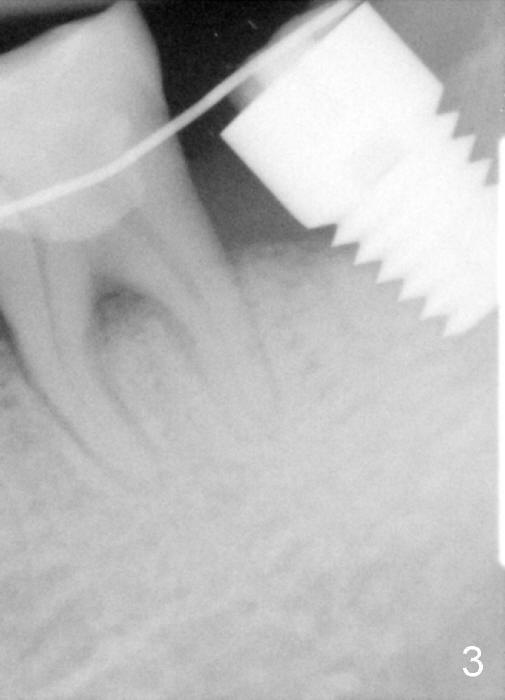

The soft tissue heals around the implant 1 months postop (Fig.1), but the implant (7x11 mm) is unstable. It should have been placed 2 mm deeper (Fig.2). It is splinted for the neighboring tooth (Fig.3). When the splint is removed 4 months later, the implant remains mobile. It is removed with infiltration anesthesia. The osteotomy is deepened by approximately 2 mm. A 7x14 mm tap is inserted with stability (Fig.4); there is apical space to be engaged further (arrowheads). A 7x14 mm implant is placed with insertion torque > 60 Ncm (Fig.5 I); an abutment (A) placed to keep perio dressing in place.